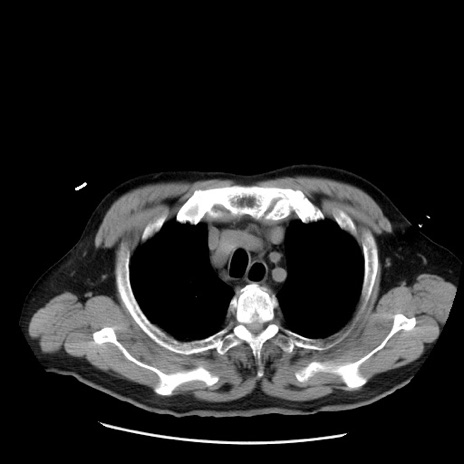

症例20(横断像)

【症例】 60歳代男性

【主訴】 腹部膨満、嘔吐

【現病歴】5日前頃より倦怠感を認め食事量減少し4日前の朝嘔吐、食事摂取困難となった。 3日前近医受診し点滴施行され整腸剤などを処方された。 当日他院を受診し、腹部膨満著明、炎症反応の上昇(CRP10.8、WBC11200)あり、紹介受診となる。

【身体所見】 意識JCS1 受け答えがはっきりしないBP 111/57mHg、 P 67bpm、、BT35.2°C、SpO2 97%(RA)、 腹部:膨隆、打診で鼓音あり、全体的に圧痛有り、腸蠕動音(-)、反跳痛ははっきりせず。

【データ】WBC 11400、CRP 14.20